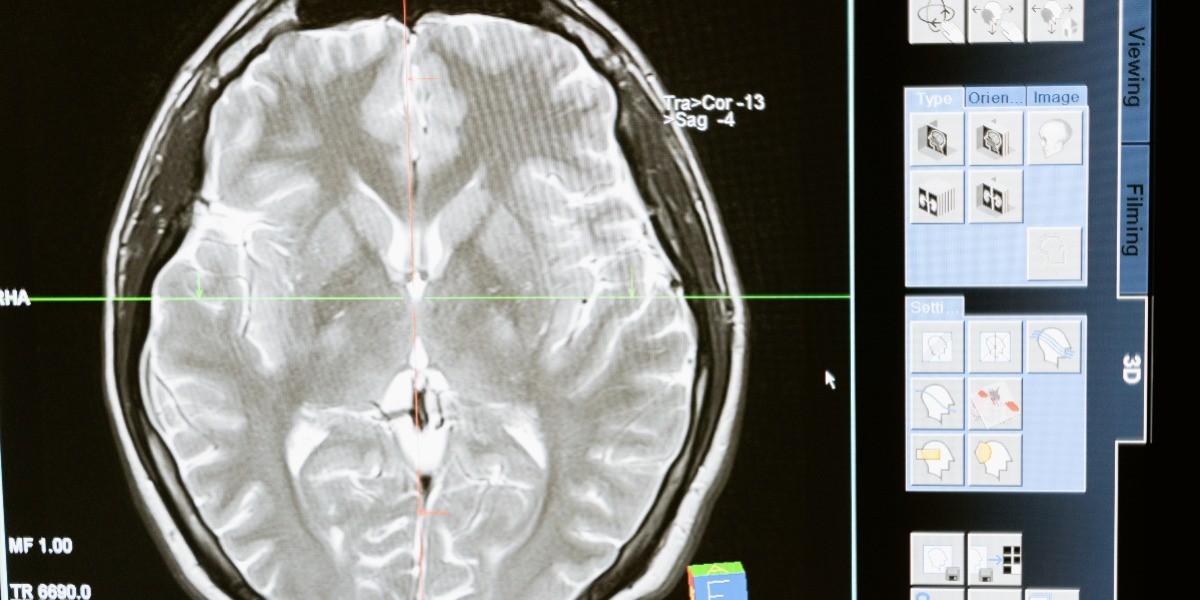

La meningitis es una inflamación de las membranas que rodean el cerebro y la médula espinal, de acuerdo con Secretaría de Salud, los bebés y menores de cinco años son especialmente vulnerables.Cada 24 de abril, se conmemora el Día Mundial de la Meningitis con la finalidad de generar conciencia sobre la importancia de su prevención a través de la vacunación.Existen varios tipos de meningitis, la más común es la meningitis viral, que ocurre cuando un virus penetra en el organismo a través de la nariz o la boca y se traslada al cerebro manifestándose con dolor de cabeza, fiebre y rigidez en el cuello. Los síntomas pueden variar y manifestarse con: